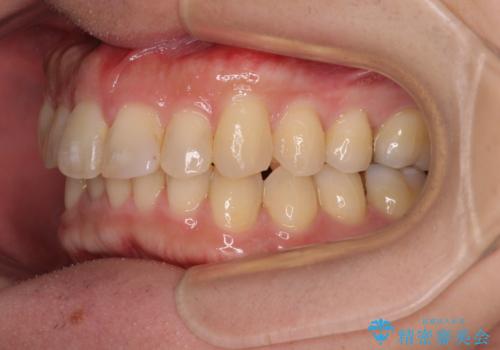

深い咬み合わせで顎が疲れる ワイヤー矯正でディープバイトを解消

- 深い咬み合わせによる食いしばりで、顎関節や頭が痛むことがあるとのことで来院された患者様です。

歯ぎしりができないくらい強い食いしばりの咬合状態であったため、奥歯の歯軸を起き上がらせることで咬合を挙上させ、歯ぎしりができるようにしていくこととしました。

下顎が左側にずれているため、上下正中は最大限合わせられるところまで合わせるゴールとなりました。